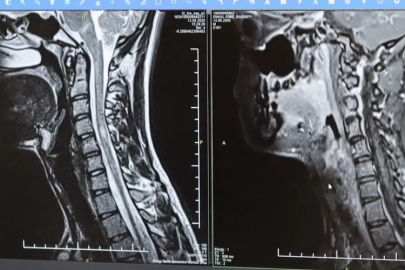

Bursa Şehir Hastanesinde görevli Nöroloji Uzmanı Prof. Dr. Özden Kamışlı, 30 Mayıs Dünya MS Günü kapsamında açıklamalarda bulundu. MS’in, bağışıklık sisteminin sinir sistemine saldırmasıyla gelişen kronik bir hastalık olduğunun bilgisini veren Prof. Dr. Kamışlı, "Dünyada yaklaşık 2.8 milyon MS hastası olduğu bilinmektedir. MS genellikle 20-40 yaş arası gençleri etkilemektedir. Bununla birlikte çocukluk döneminde ya da ileri yaşta da ortaya çıkabilmektedir. Kadınlarda görünme sıklığı erkeklere göre bir buçuk kat daha fazladır" dedi.

MS hastalarının çeşitli şikâyetlerle hekimlere başvurduğunu vurgulayan Kamışlı, "Bunlar arasında görme bozukluğu, kol ve bacakta kuvvetsizlik, uyuşmalar, dengesizlik, yürüme bozukluğu, idrar problemleri veya aşırı yorgunluk ve halsizlik hali bulunmaktadır. MS ataklarla seyredebilir ve genellikle en sık görülen formu budur. Birdenbire bir şikâyet ortaya çıkar ve zamanla azalır veya kaybolur. Bir de progresif dediğimiz ilerleyici formu vardır. Bu ilerleyici formda hastalık yavaş yavaş ilerlemektedir. MS her hastada farklı seyreder. Bu nedenle tek tip bir MS hastalığından bahsetmek mümkün değil" şeklinde konuştu.

Hastalığın tanısını ne kadar erken konulursa ve tedaviye ne erken başlanırsa; hastaların günlük hayatta aktif ve üretken bir şekilde devam etmelerinin o kadar kolaylaştığına dikkat çeken Kamışlı, "Günümüzde MS'le ilgili çok fazla gelişme oldu ve tedavi seçenekleri arttı. MS merkezlerinde bu tedavi seçeneklerine ulaşmaları mümkün. Hastalarımız için doğru tanı, düzenli takip ve uygun tedavi oldukça önem teşkil etmektedir" diye konuştu.